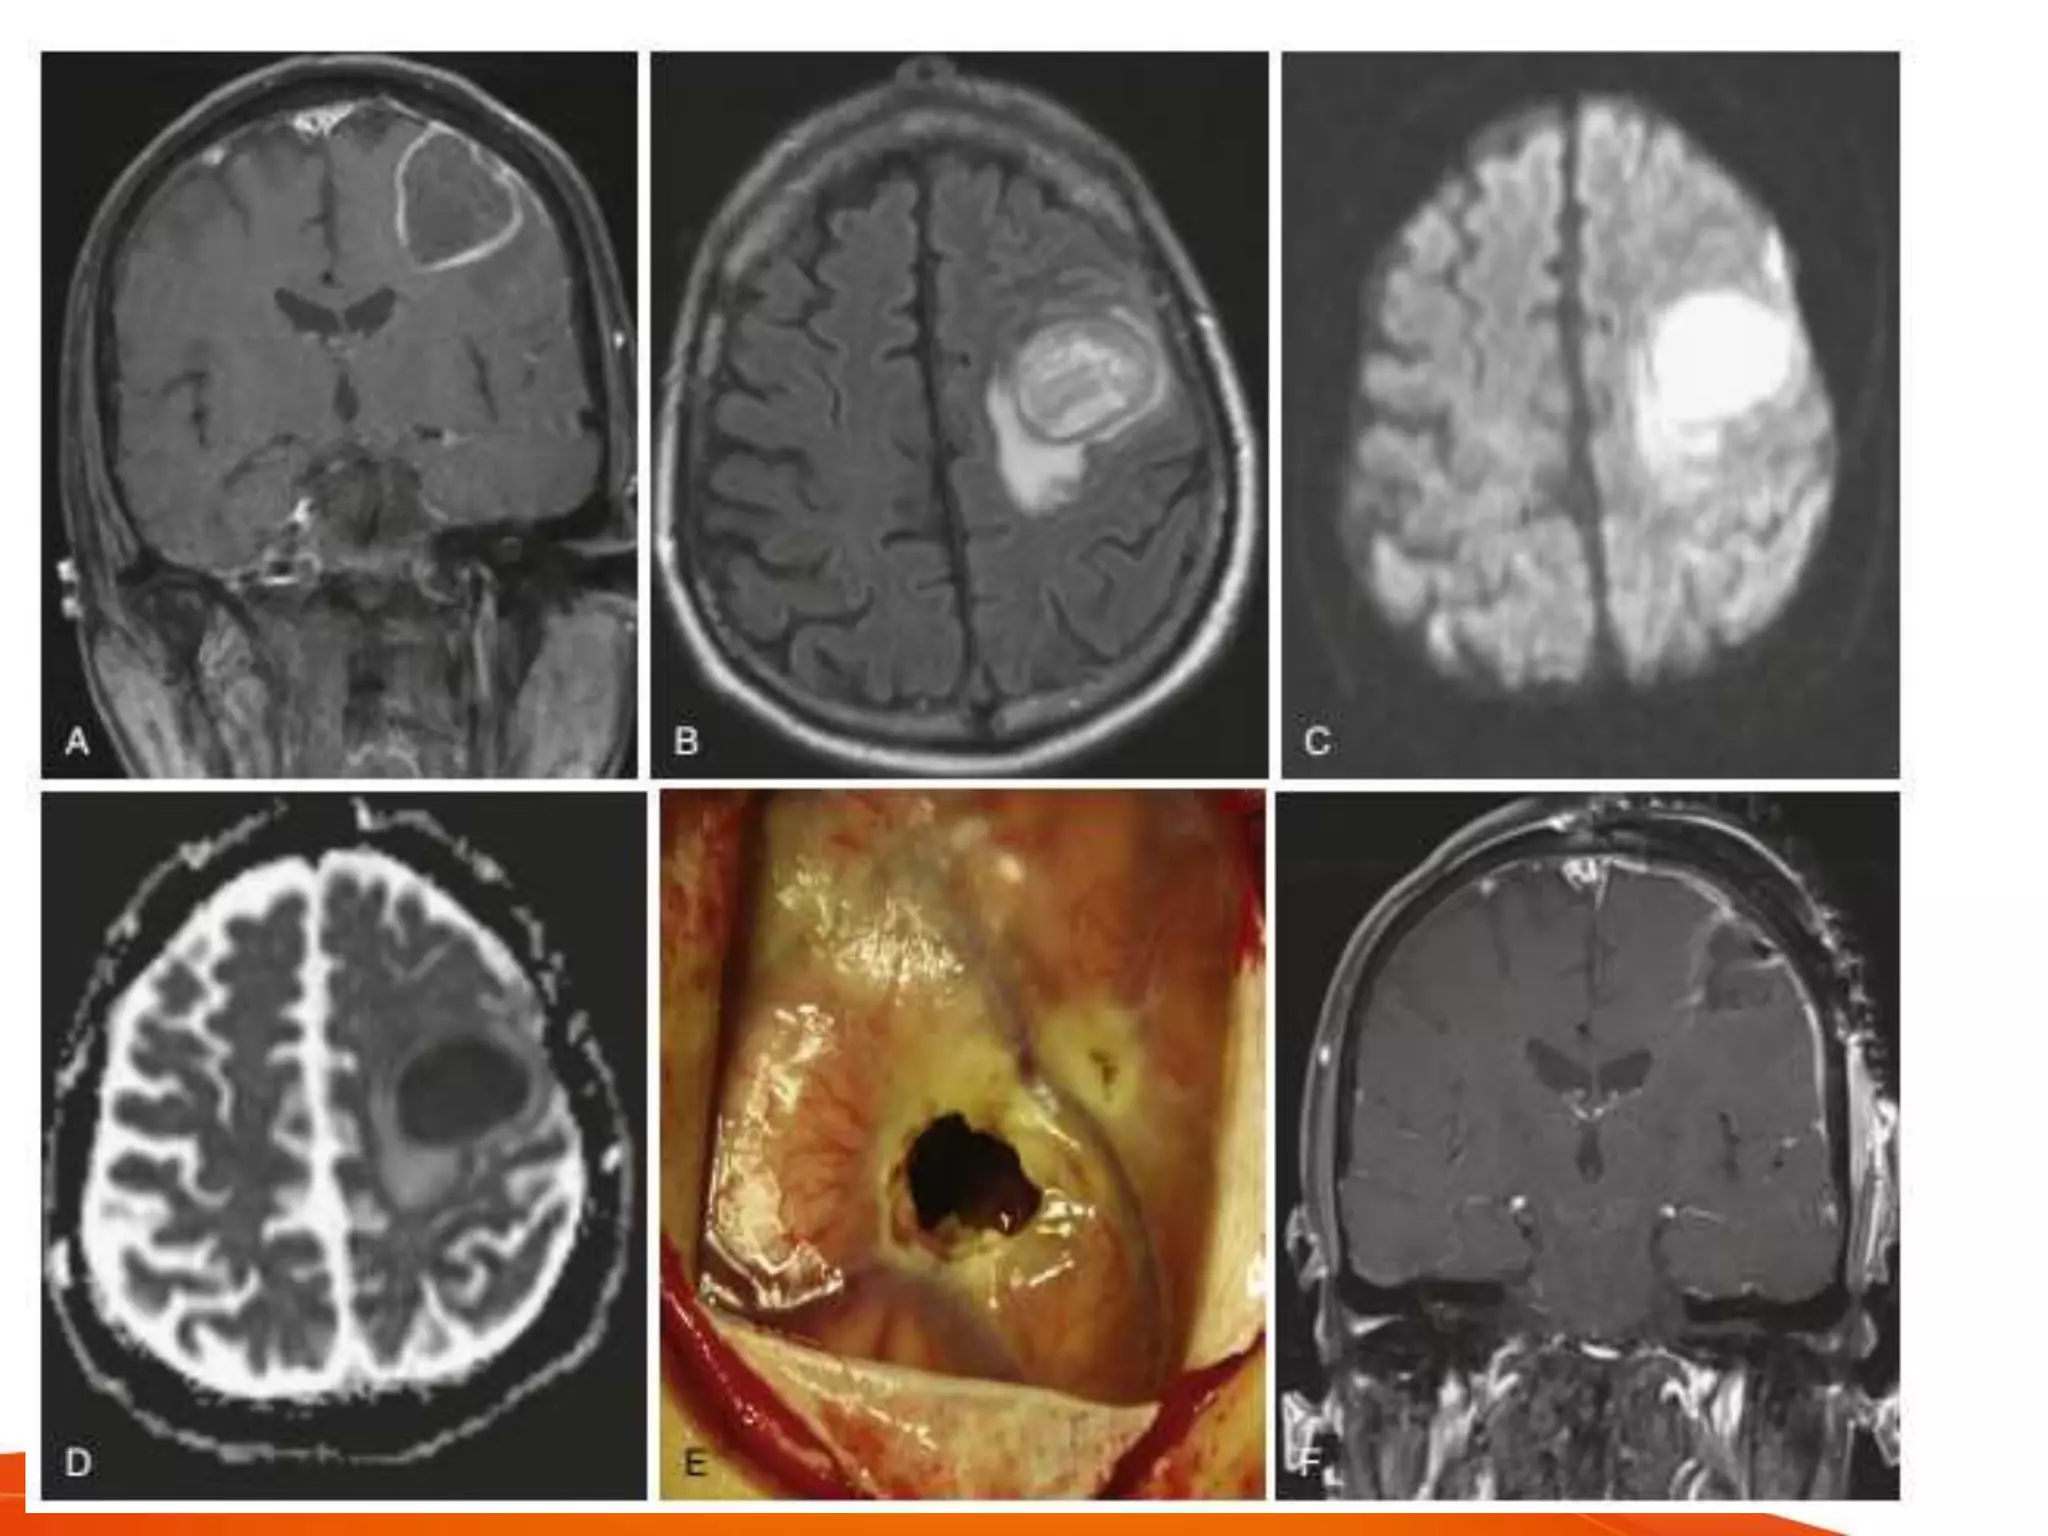

SURGICAL EXCISION

• useful in

– large (>2.5cm) abscess

– superficial abscess

– refractory aspirations

– posterior fossa lesions

– fungal abscesses

– post traumatic abscess with retained bones or

foreign bodies

– gas containing abscesses

• not choice in

– cerebritis stage

– deep seated abscess

– eloquent areas

• emergency surgery in

– obtunded patient

– severe neurologic deficit

– encapsulated lesion

– aim to decompress and diagnose

• choice procedure

– image guided keyhole approach

– small incision

– limited craniotomy

– limited brain retraction

– minimal intraop trauma

– better cosmesis

• large craniotomy and decompression

– failed conservative management

– dangerios location like posterior fossa

– extensive edema, mass effect

– impending or actual hydrocephalus